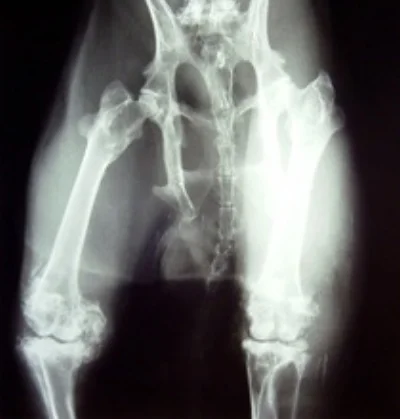

ARTHRITIS IN RABBITS

Arthritis is a painful inflammation and stiffness of the joints. Signs include:

Some rabbits develop arthritis naturally due to age or genetics and it grows to be a disability for them. Other rabbits may develop arthritis due to another condition or injury they have had. It can develop in rabbits that have fractured their spine and lost mobility in their hind legs, rabbits that have splay legs, rabbits that have broken or malformed legs, and rabbits that have had one or more legs amputated. In these rabbits, arthritis commonly develop over timebecause the remaining “healthy” legs have to compensate for the one/ones that are not operating properly. This adds stress to the joints and can lead to arthritis. Most arthritis is not fixable but it can be managed. Massage and other forms of physical therapy can help to exercise and ease tension in the joints and sometimes can help relieve arthritis symptoms.